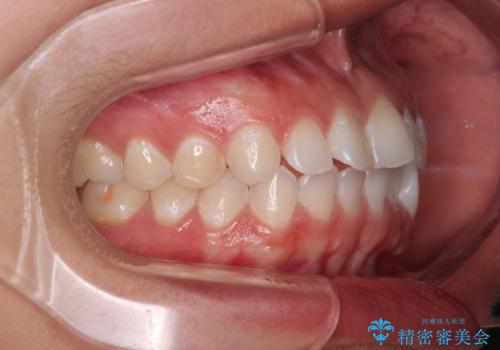

- 上下前歯のデコボコを気にして来院された患者様です。

ワイヤー矯正でもマウスピース矯正でも可能でしたが、短期間で、自身の手を煩わせることなく治療を行いたいとのことで、ワイヤー装置にて矯正治療を行うこととしました。

僅か半年強、あっという間に治療を終えることができました。